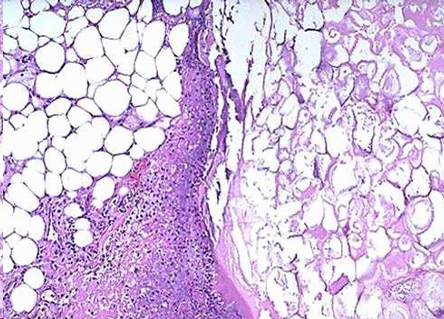

Necrosis grasa:

Necrosis de adipocitos que liberan grasas neutras acumuladas en su citoplasma y que posteriormente se unen a iones Na, K o Ca, ocurre la saponificacion.

Aspecto microscopico:

- Adipocitos límites irregulares

- Núcleos picnóticos (condensados)

- Citoplasma opaco y eosinófilo

- Reacción inflamatoria periférica